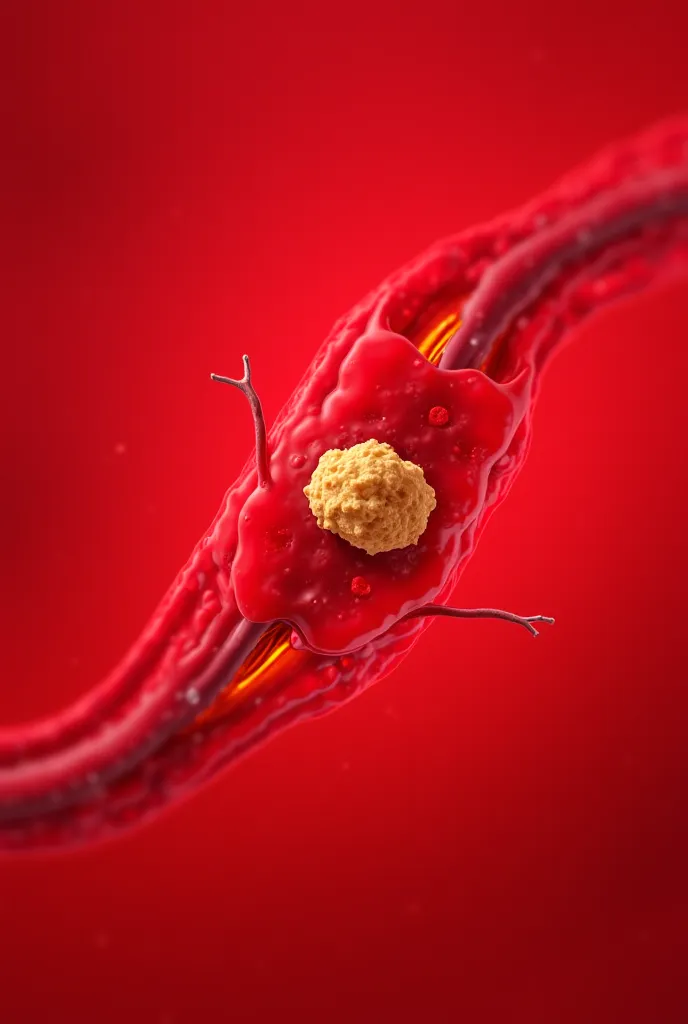

Pictures of swollen thyroid gland in neck, Use a Canon EOS 5D Mark IV with a 24

pictures of swollen thyroid gland in neck, Use a Canon EOS 5D Mark IV with a 24-70mm f/2.8 lens. Settings: ISO 100, aperture f/8, and shutter speed 1/125s to capture a sharp, vibrant image with a wide depth of field.

pictures of swollen thyroid gland in neck